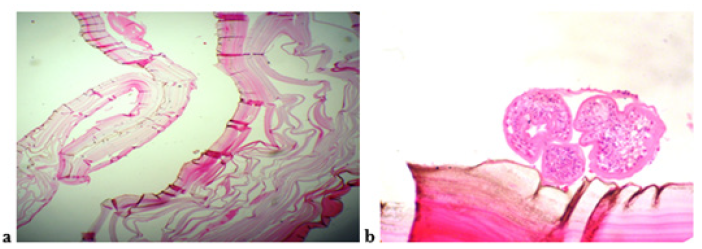

Figure 2: A cellular laminated membrane of the cyst wall (a). Protoscolices and brood capsule are also present (b).

Previous CT abdomen and pelvis examination was also reviewed for comparison. There is redemonstration completely collapsed fragmented body of L3 vertebra with severe spinal canal stenosis. Redemonstration associated loculated collection in bilateral psoas muscles and prevertebral location. She underwent anterior decompression of L3 vertebral body and multiple hydatid cysts were removed. Hypertonic saline solution was used during surgery. Histological examination confirmed the hydatid cysts (Figure 2).

Figure 1: The cyst wall is composed of a cellular laminated membrane (long arrow) and an inner nucleated germinal layer (arrow). Protoscolices and brood capsule (arrowhead) are present.

Histopathological evaluation shows three layers of hydatid cyst. The inner most germinal layer is thin. The embryonic tape worm, scolices, develops from an out pouching of the germinal layer and form hydatid sand, settling into the dependent parts of cyst (Figure 1). She was given albendazole 2 tablets twice daily for 2 months.